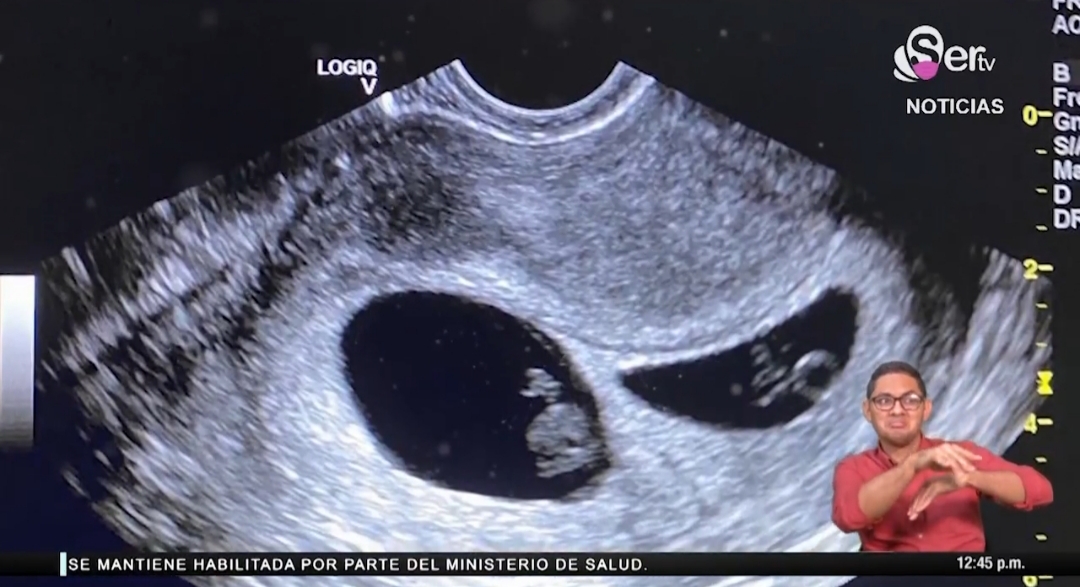

El primer procedimiento se realizó el 24 de enero de 2020 resultando una prueba de embarazo positiva. Luego para su sorpresa, en el ultrasonido se muestra que eran dos embriones con latidos. También nos relatan que el viernes 2 de octubre era una fecha de control para la cesárea, pero le adelantaron el procedimiento para ese mismo día porque Yanilka tenía la presión alta.